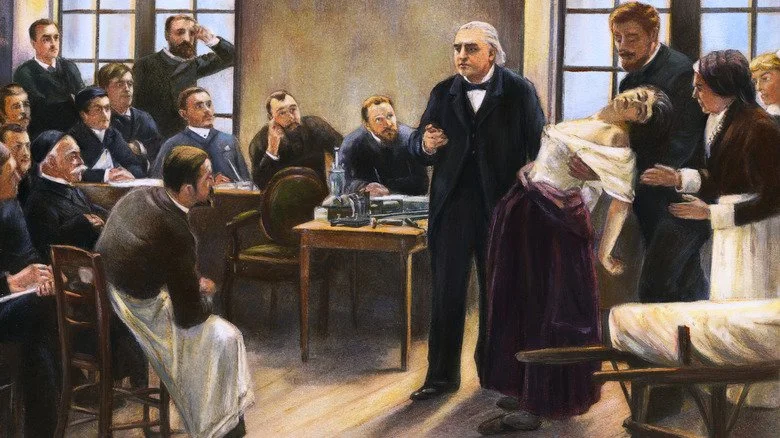

Pendant une grande partie de l’histoire, être une femme nécessitant des soins médicaux était une situation particulièrement difficile. L’un des exemples les plus frappants est la notion d’« hystérie ». Cette idée, courante au début du 19ème siècle, remontait en réalité à plusieurs générations auparavant. Les anciens Grecs pensaient par exemple que l’utérus pouvait se déplacer à l’intérieur du corps et provoquer toutes sortes de troubles.

Pour empêcher cet organe supposément errant d’étouffer ou d’écraser les autres organes, on avait recours à des méthodes étonnantes : placer des odeurs offensantes près de la tête pour faire fuir « l’utérus » et des parfums agréables à l’extrémité opposée du corps. Cette théorie fut contestée par certains, comme le médecin antique Galien, qui rejetait le déplacement de l’utérus mais admettait d’autres idées tout aussi surprenantes, comme la présence d’« esprits animaux » censés animer la pensée.

Malgré les progrès de la médecine, les médecins du début du 19ème siècle continuaient à attribuer de nombreux troubles féminins à l’hystérie. Certains, tels que Philippe Pinel, défendaient une approche plus humaine envers les patientes, bien que cette bienveillance se teintait souvent de paternalisme. Cette étiquette médicale servait surtout à isoler les femmes décrites comme trop émotionnelles, irrationnelles ou atteintes par cet « utérus encombrant », en les excluant de certains emplois et domaines sociaux.

Ce qui est sans doute le plus étonnant, c’est que le diagnostic d’hystérie n’a été officiellement abandonné par la plupart des sociétés professionnelles de psychologie qu’à partir des années 1980.